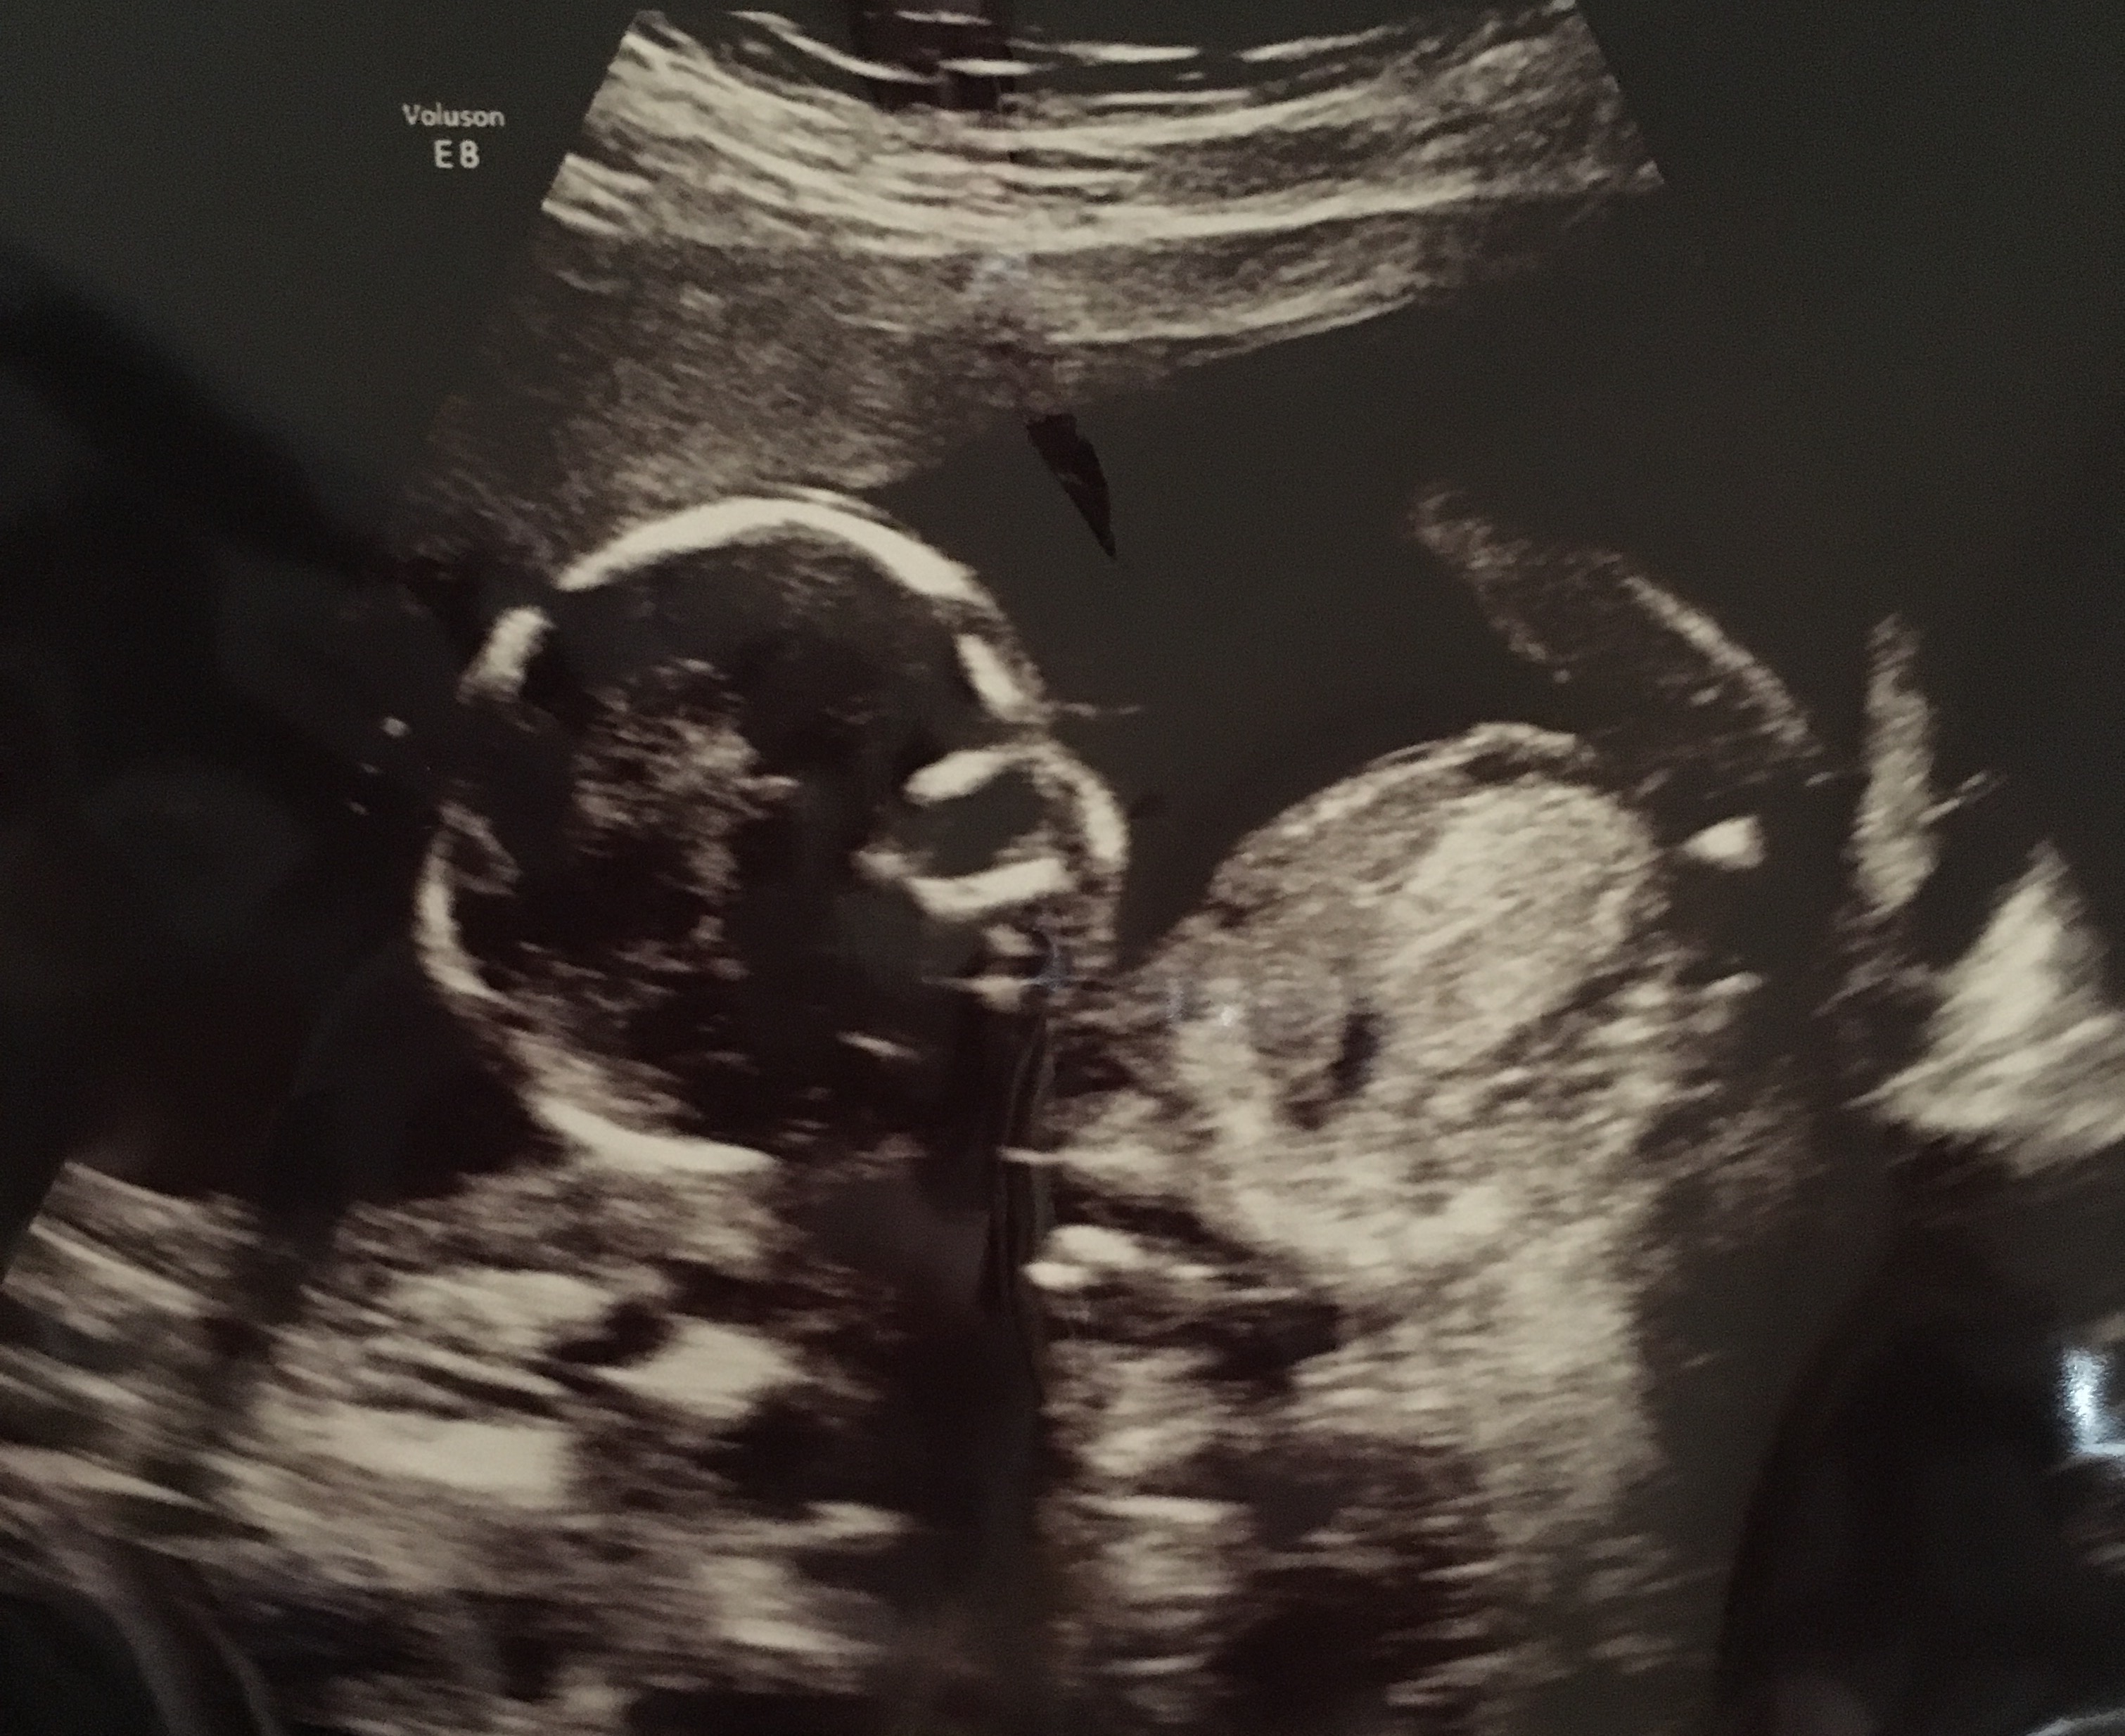

Had a scan at 17 weeks. Is this white mark/blob by the legs (I think) a willy?!

Yes, it was a gender scan. Baby did lots of potty shots but she said it had the cord between its legs. Then when it was in a side view profile she said boy. Just wanted to know that pic shows he's a boy as I didn't come away with a pic showing that he is one, id have liked a potty shot. I will ask at 20 week scan though!

I didn't know that about it maybe being unreliable at 17 weeks. I'm sure he is a boy but I will ask at my 20 week scan. I just wondered if that mark was it, as I didn't get a potty shot or anything.

IT could go either way. it would be very high for a penis. And a penis isn't so white on a ultra sound.

That is not a willy, but it could still be that the tech saw a willy during the scan. Do you have any nub (side view) shots from 12-14 weeks?

No that doesn't look like a penis to me, it's too white. I have a pic of my DS2 at 16 weeks from the side and his penis is sticking straight up with a bump on the top of it. It's also more transparent looking than what I see in your pic. Unless I'm mistaken, an opaque white area is likely to be bone. What we're seeing might be part of the baby's leg.

I'm sure if she said then she did see it but I don't think the picture shows gender I'm afraid.